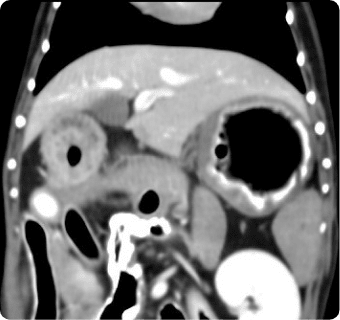

진단하는 핵심센터입니다. 고화질 CT와 초음파, 디지털 엑스레이, 투시촬영기기(C-arm)을 사용해

빠른 촬영속도를 통해 마취시간을 최소화 하며, 선명한 3차원 영상을 구현합니다.

종양, 전이평가, 선천적 혈관 기형 등 여러 질환의 조기 발견 및 환자상태를 평가합니다.

간, 비장, 소화기, 콩팥, 방광, 부신의 종양, 간문맥전신단락, 복강 내 실질 장기 평가, 요로결석에 의한 폐색 평가